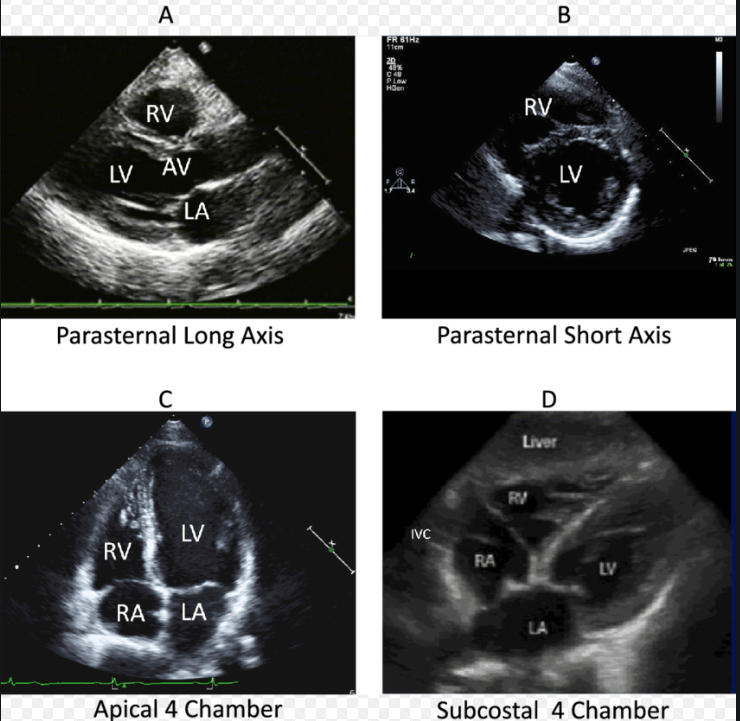

그러나 심혈관 검사(심전도, 흉부X선, 심장초음파)에서 이상이 발견되지 않으면 소화기계 질환의 원인도 고려해야 합니다. 이 경우 약물 치료의 반응을 보거나 위 카메라로 식도염, 위염, 궤양 질환 등을 확인합니다.▶ 심장 초음파는, 심장이나 판막의 구조, 이상 소견을 실시간으로 확인하는 검사입니다. 심장 주변의 삼출액, 판막이상, 심장근육질환, 협심증 유무를 확인합니다.

초음파 탐침(probe)을 흉부에 대고 심장의 몇 부위를 검사하였으며 검사 소요 시간은 20-30분 정도입니다.

※ 심장 초음파 기본 VIEW

출처 : researchgate.net